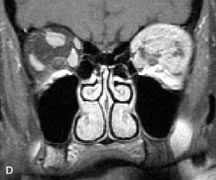

Inflammatory and Lymphoproliferative Lesions

Inflammatory conditions of the orbit, both idiopathic (inflammatory pseudotumor) and those of known causes, have been found to be hypointense to fat and isointense to muscle on Tl-weighted studies and isointense or slightly hyperintense to fat on T2-weighted images (Fig. 21).50,64,69 The more fibrous or sclerosing varieties have less signal intensity on T2-weighted images. Marked enhancement is seen in pseudotumor infiltrates after gadolinium administration.70 The same signal characteristics are demonstrated in patients with Tolosa-Hunt syndrome, with mass lesions seen in the cavernous sinuses and orbital apices.71

Fig. 21. A. T1-weighted MR scan demonstrates diffuse enlargement of both the superior rectus and levator palpebrae superioris muscles (single arrows). The involvement of the tendinous insertions and preseptal soft tissues (open arrows) as well as lack of involvement of other muscles helps differentiate this entity from thyroid-associated orbitopathy. B and C. Postcontrast fat-suppressed T1-weighted MR scans demonstrate extensive enhancement of the involved muscles as well as the preseptal (open arrows) and perinuscular tissues (double arrows).

Lymphomas have MRI characteristics similar to those of inflammatory lesions in that they are hypointense to fat and isointense to muscle on T1-weighted images (Fig. 22). They may appear hyperintense to fat on T2-weighted images, perhaps owing to less fibrosis than that seen in orbital inflammatory pseudotumor, although this is not a consistent finding.31,50,66 Lymphoid tumors typically enhance moderately after contrast injection. Unfortunately, studies have shown that tumor density and homogeneity are similar between inflammatory and malignant orbital infiltrates, and MRI cannot differentiate these lesions.72,73

Fig. 22. A and B. T1- and (C) T2-weighted MR scans demonstrate a poorly defined multicompartmental mass enveloping the lateral rectus, superior rectus, and levator palpebrac superioris muscles. The lesion is isointense to brain on T1- and T2-weighted scans, as is typical for highly cellular neoplasms. D. Postcontrast fat-suppressed T1-weighted scan demonstrates intense enhancement of the infiltrating intraconal and extraconal tumor.